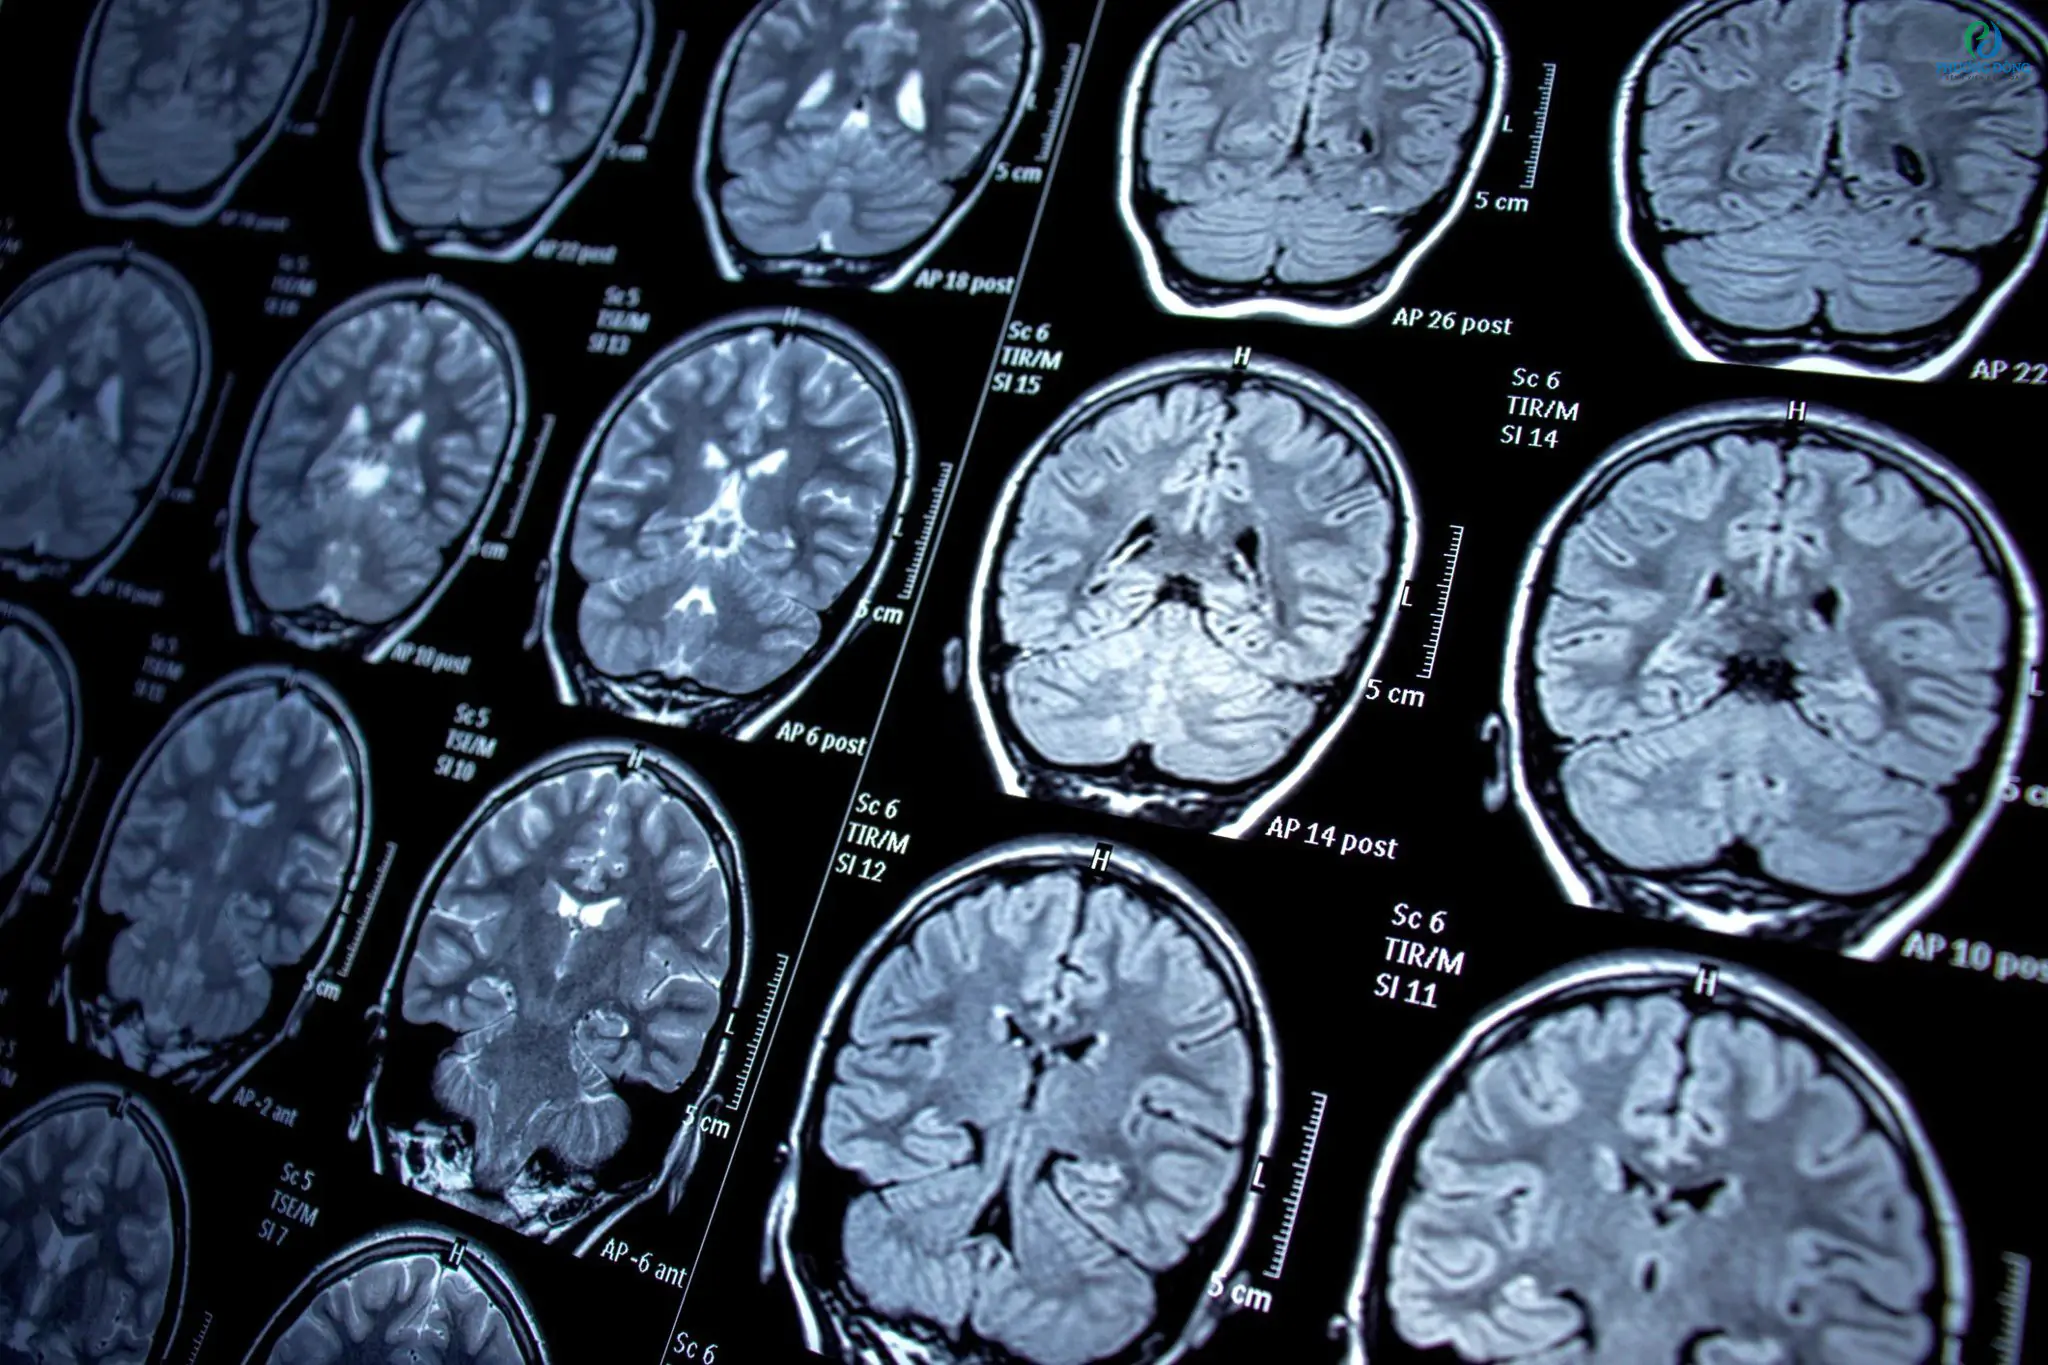

Bác sĩ sẽ quyết định chụp CT, MRI não +/- cản quang, chọc dò dịch não tủy, hoặc làm xét nghiệm máu trong các trường hợp nghi ngờ đau đầu thứ phát hoặc có dấu hiệu “red flags” như đã nêu.